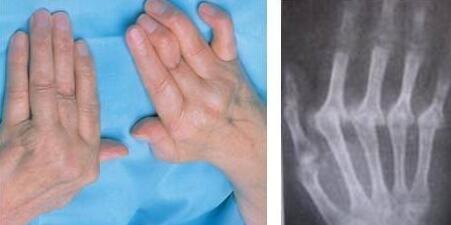

郑州风湿病医院专家表示:类风关虽然是一种关节炎,但它产生的损伤不是关节的机械磨损;这是一种免疫性疾病,免疫系统错误地把自己的组织当做外来物质进行攻击。...[详细]